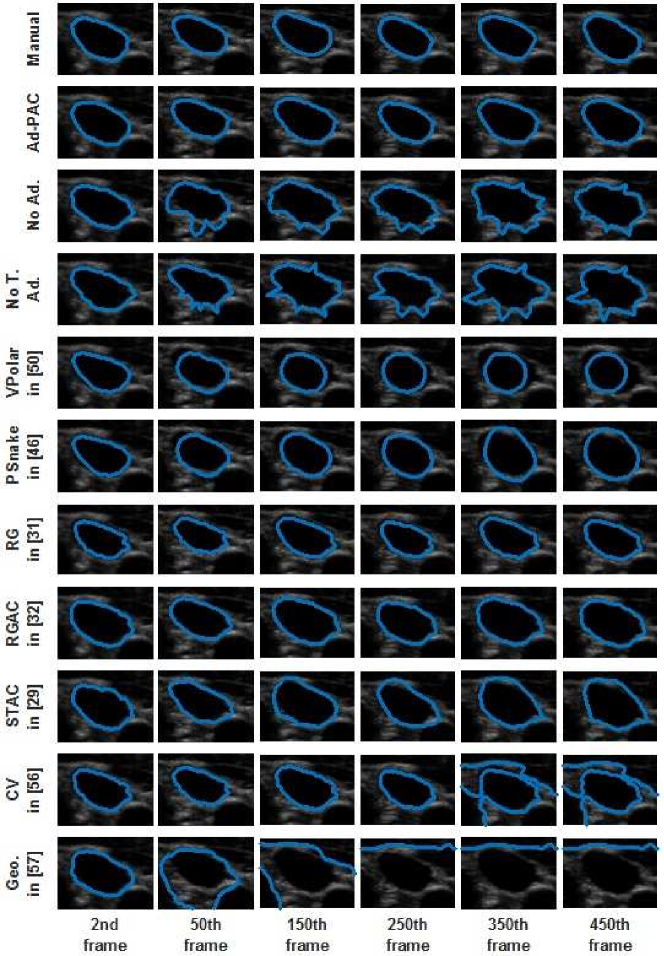

Ad-PAC performance was compared to expert manual segmentation, Ad-PAC without parameters adaptation, Ad-PAC without temporal adaptation, and two current state-of-the-art polar AC algorithms introduced in Section II [50, 51]. Additionally, it is also compared to region growing (RG) [31] and its combination with AC (RGAC) [32], Speckle tracking driven AC (STAC) [29], and two classic AC algorithms - Chan-Vese [56] and Geodesic [57]. For each of these algorithms, parameter optimization was accomplished using a small subset of videos with variable image quality. For each video, the first frame was manually segmented by an operator with subsequent frames segmented automatically.

This Section compares the tracking performance of the proposed Ad-PAC algorithm with the manual segmentation and other algorithms as per section V for two sample video as shown in Figs. 12 and 13, respectively. From both figures, it is evident that the proposed Ad-PAC algorithm outperforms the existing algorithms and produces results very close to the manual segmentation. Further supporting evidence that parameter adaption significantly improves the performance is evident in rows 3 and 4 row of Figs. 12 and 13. The segmented contour is not smooth without parameter adaptation (which is observed as spikes) suggesting that the weight given to the curvature energy term was not sufficiently large enough to compete with the other energy terms and consequently, dominated by them.

Fig. 14 presents the DICE factors obtained from each algorithm, averaged across all 65 videos irrespective of IJV shape, intensity, speed of variation and quality. From this figure, it is clear that the proposed Ad-PAC algorithm outperforms all existing algorithms with its corresponding DICE factor greater than 0.64. Other algorithms perform significantly worse. In the following sub-sections, more detailed results are presented.